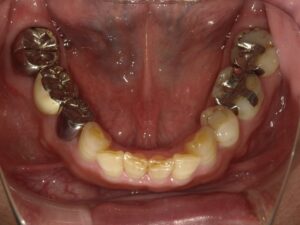

術前・術後写真

【術後】

最終的な被せ物(セラミッククラウン)の型行い取りを行い、いよいよ完成したセラミックの被せ物が入りました。

インプラント部分は本物の歯のように自然でしっかりと噛めるようになりました。

右下7番の状態が悪い患者さんでした。骨吸収を起こしており動揺もでていたので、抜歯も考えましたが、インプラントを選択されたので、骨吸収像は見られますが、動揺はほぼ無くなり噛めている状態を維持されています。インプラントは他の歯を守ることができる治療法だと思えた症例となりました。